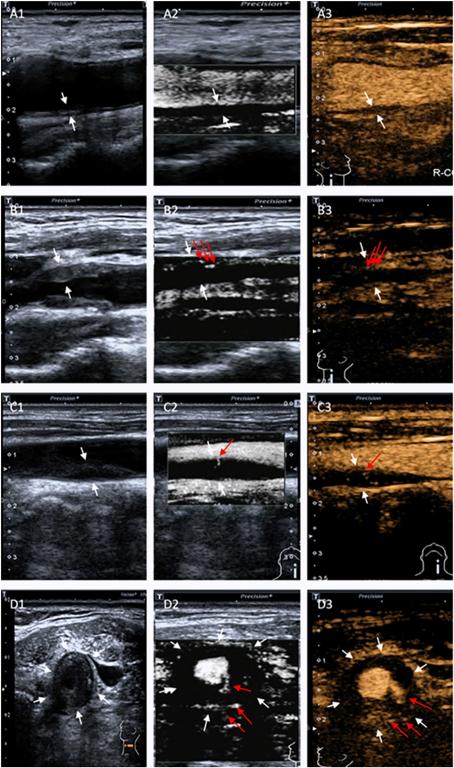

图1 常规超声、SMI及超声造影分级

研究结果显示两名超声医师在应用SMI和CEUS方法诊断颈动脉斑块新生血管方面高度一致。SMI与超声造影评价颈动脉斑块的新生血管分级结果一致。SMI和CEUS分级与斑块厚度呈正相关。研究表明CEUS和SMI对评估斑块的新生血管有很高的诊断价值。